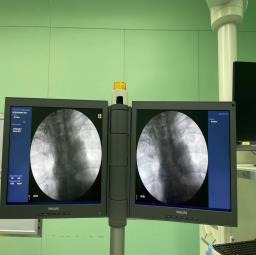

随后,顾明主任与盐城市第三人民医院介入科副主任医师潘杰进行了沟通,潘杰主任了解了两位患者的病情及身体状况后,在盐城瑞康医院的配合下,克服了可能出现的麻醉意外、术中大出血、静脉血栓栓塞等多重风险,经过40分钟的输液港植入术,不仅为两位患者建立了长期有效的输液通路,同时提高了患者的生活质量,保障了患者的各项治疗得以顺利进行。

输液港工作原理图